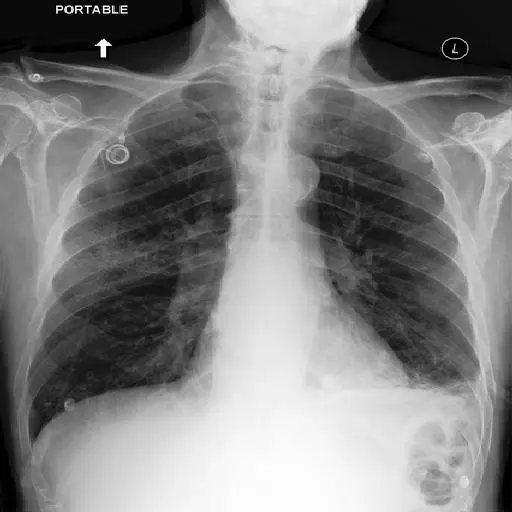

Cogninn is collaboration with university hospitals and private health centers develops custom AI solutions for image to text applications for clinical diagnosis applications.